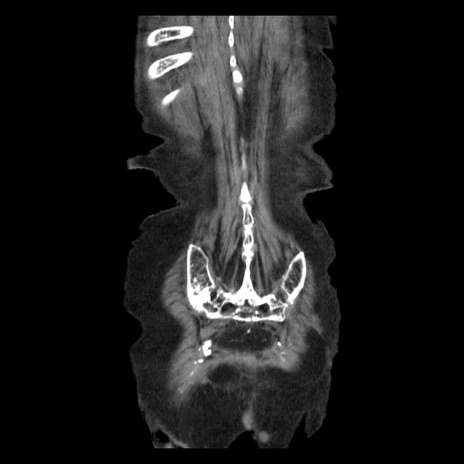

症例14(冠状断像)

【症例】 90歳代女性

【主訴】 腹痛・嘔吐

【現病歴】今朝から左側腹部痛を認めた。 経過観察していたが、嘔吐を認めたため来院。

【既往歴】 子宮癌術後

【身体所見】 意識清明、BP 127/54mmHg、P 98bpm Sp02 95%(RA)、BT 35.8°C、腹部平坦・軟腸ぜん動音聴取良好、右下腹部圧痛(+) 反跳痛なし

【データ】WBC 9800、CRP 0.46